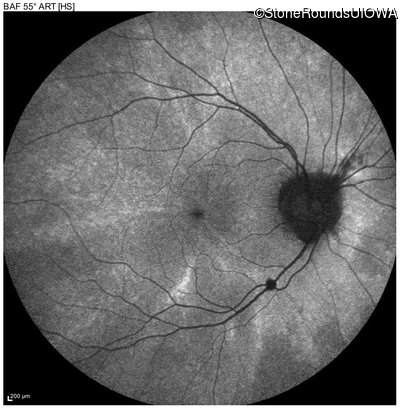

Blue Autofluorescence - Right - 20/20

Exemplar